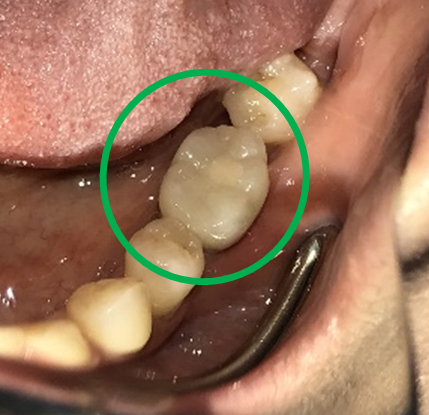

ブリッジの支台になっている奥の歯が、被せ物の中で虫歯になり、支台の役割を果たさず、前方の歯のみで支えられていました。前方の歯をそのままにして、後方の部分を切り離すと、そのまま取れてきました。中は、虫歯で歯根しか残っていない状況でした。この歯は、根管治療後、単独でオールセラミック冠を被せ、歯のないところにインプラントを埋入しました。

冠はブリッジを切断しただけで取れてきました。軟化象牙質を取り除いたところ、歯根しか残っていない状況で保存できるかどうかのぎりぎりのところでした。

After